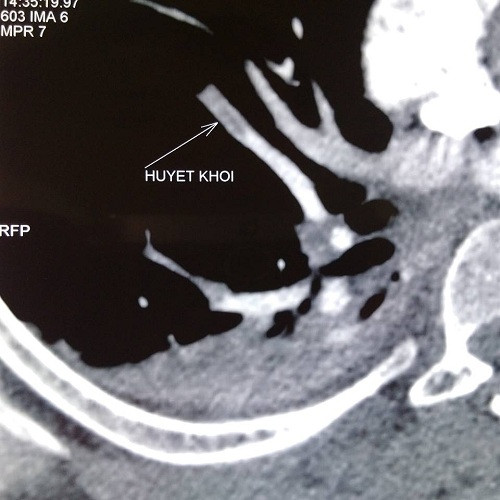

tắc động mạch phổi

Hình ảnh Cắt lớp vi tính động mạch phổi, có tắc nhánh 7, 8 động mạch phổi (P) sau mổ viêm phúc mạc tiểu khung. Ảnh: BSCC.